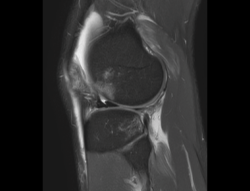

1.2. Ligamentos

Se visualizan como estructuras lineales hipointensas en todas las secuencias.

1.2.2. Ligamento cruzado anterior (LCA) (Figuras 40, 41, 42, 43 y 44)

Figura 40. Corte de secuencia sagital T2 Fat-Sat de resonancia magnética de rodilla: ligamento cruzado anterior normal.